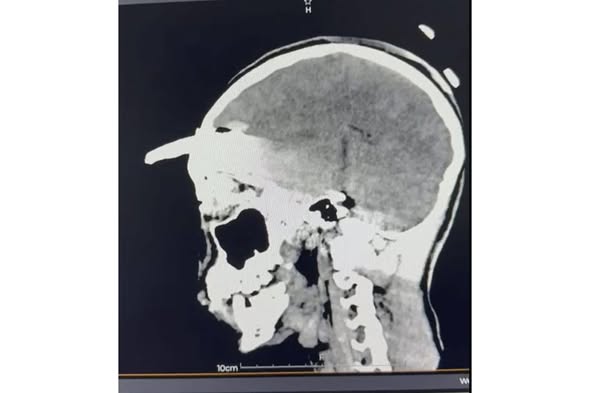

El joven de 15 años fue sometido a una intervención de cuatro horas, donde sin afectar tejido cerebral, le fue retirado un machete curvo.

Personal médico del IMSS Yucatán logró salvar la vida de un adolescente de 15 años que llegó con una herramienta agrícola INCRUSTADA en el cráneo. Tras ser trasladado de emergencia desde Acanceh, el paciente recibió atención en el Hospital General Regional No. 1, donde especialistas en neurocirugía, pediatría y terapia intensiva coordinaron una intervención de alta complejidad para retirar la coa metálica sin causar daño cerebral.

El procedimiento, liderado por el neurocirujano Luis Víctor Ornelas González, tuvo una duración aproximada de cuatro horas y requirió estudios de imagen avanzados, manejo antimicrobiano especializado y seguimiento continuo en terapia intensiva pediátrica.